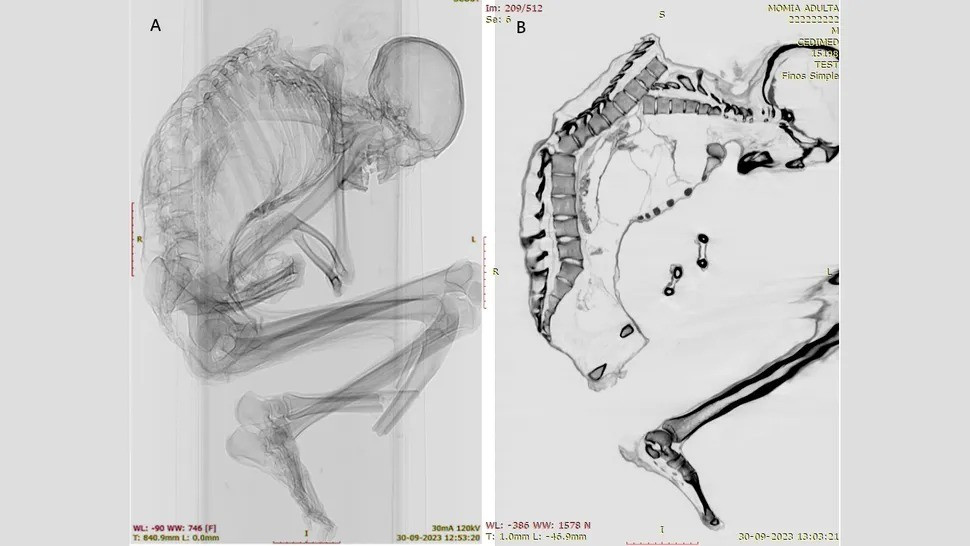

Kết quả kiểm tra xác ướp tìm thấy gần một mỏ ngọc lam ở sa mạc Atacama cho thấy người đàn ông này là một thợ mỏ tử vong trong vụ tai nạn lao động thương tâm.